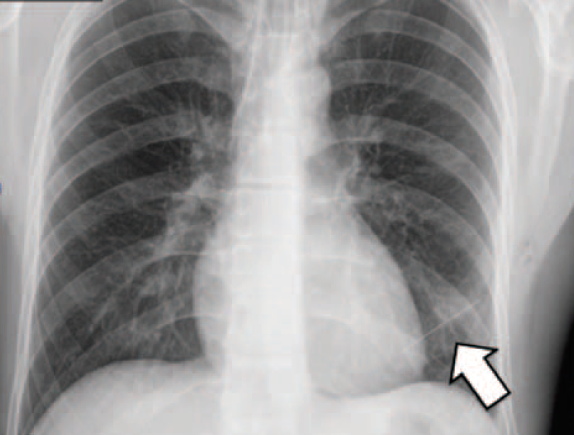

Here's a chest X-ray that made the radiologist gasp and reach for the phone. What could this thin grey line possibly be? The patient was a 30 yo male, no significant medical history, who had started to experience stabbing pains in his chest a few days earlier.